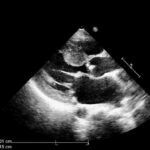

At Ultrasonu (4/19)

Veteriner ayrıca kısrağın sağlığını belirlemek için başka birçok test yaptı. Hassas bir hamilelik olmaması gerekiyordu ama emin olmak istedi ve şu anda sahip olduğu aletlerle yapabileceği her testi yaptı. İlk testlere göre her şey yolunda görünüyordu. Ancak hamileliğin ilerleyen dönemlerinde işler planlandığı gibi gitmedi…